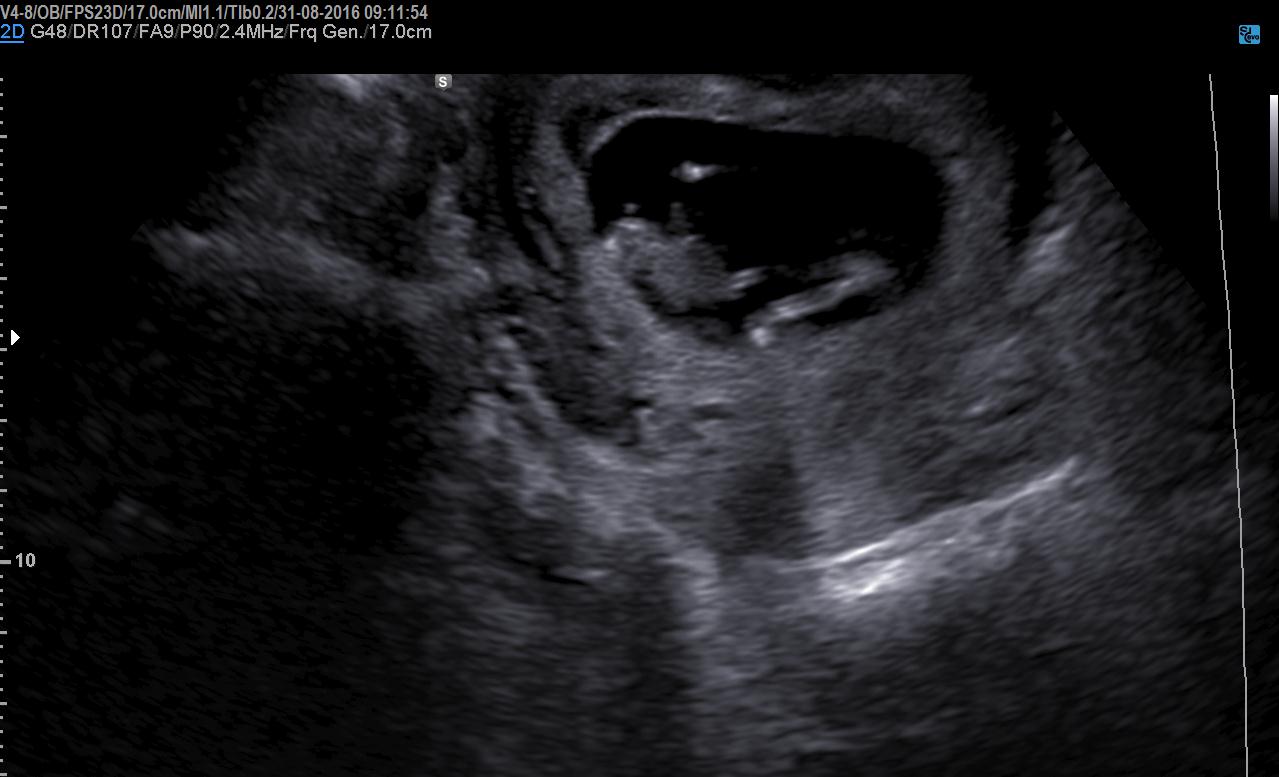

Hi everyone. Herw is my 12 week sonar. Really excited... can anyone determine my little blessings gender? I think boy but not 100% sure... Opinions???Attachment 32950Attachment 32951

Boy or Girl??☆☆